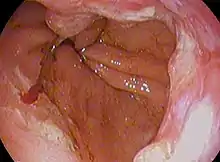

Endoscopic image of an esophageal adenocarcinoma

Esophageal cancer is cancer arising from the esophagus—the food pipe that runs between the throat and the stomach.[2] Symptoms often include difficulty in swallowing and weight loss.[1] Other symptoms may include pain when swallowing, a hoarse voice, enlarged lymph nodes ("glands") around the collarbone, a dry cough, and possibly coughing up or vomiting blood.[1]

The two main sub-types of the disease are esophageal squamous-cell carcinoma (often abbreviated to ESCC),[9] which is more common in the developing world, and esophageal adenocarcinoma (EAC), which is more common in the developed world.[2] A number of less common types also occur.[2] Squamous-cell carcinoma arises from the epithelial cells that line the esophagus.[10] Adenocarcinoma arises from glandular cells present in the lower third of the esophagus, often where they have already transformed to intestinal cell type (a condition known as Barrett's esophagus).[2][11] Causes of the squamous-cell type include tobacco, alcohol, very hot drinks, poor diet, and chewing betel nut.[3][4] The most common causes of the adenocarcinoma type are smoking tobacco, obesity, and acid reflux.[3]